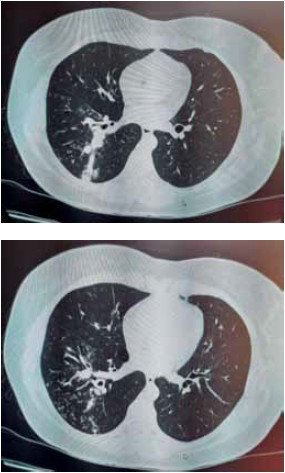

Paciente mulher, 34 anos, chega ao ambulatório com queixa de tosse produtiva, secreção mucosa, há 3 meses, sem outras queixas. Não apresenta alterações no exame físico. Solicitada tomografia computadorizada de tórax apresentada nas imagens a seguir.

Após a confirmação da etiologia do quadro pulmonar deve ser solicitada sorologia para infecção pelo